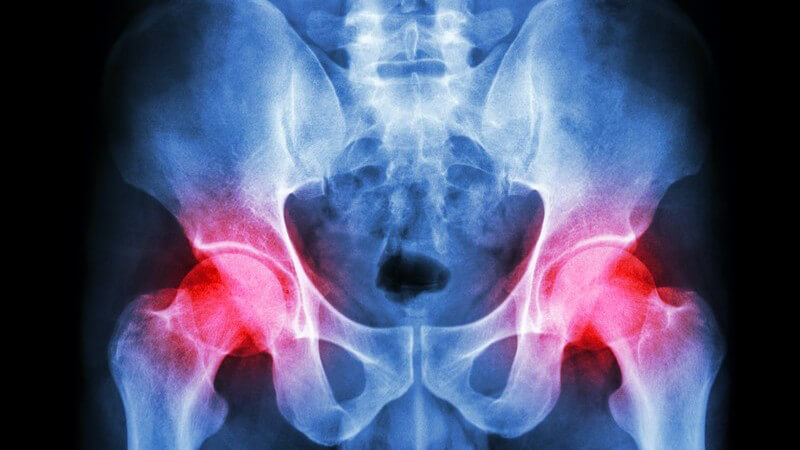

Diagnostiziert wird eine Hüft-Luxation normalerweise durch eine Röntgenuntersuchung. Dabei lassen sich auch mögliche weitere Verletzungen wie Knochenfrakturen feststellen.

Allerdings sind bei einer Hüftverrenkung oftmals weitere Untersuchungen erforderlich, um das Ausmaß der Verletzung erkennen zu können. Dazu gehören unter anderem eine Computertomographie (CT) oder eine Magnetresonanztomographie (MRT).